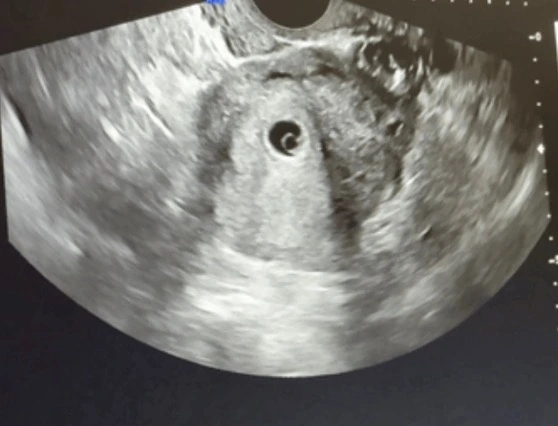

산부인과에 오기 2주 전, 건강검진에서 자궁경부암 초음파검사를 할 당시, 자궁 안에는 아무것도 없었다. 그런데 오늘, 6주라고 한다. 심장소리가 우렁찼다. 도대체 그 사이에 자궁 속에서 무슨 일이 벌어진 것일까.

지금의 임신은 나에게 그런 것이었다. 나쁜 짓을 한 것이 아닌데, 나쁜 짓을 한 것처럼 아무에게도 말할 수 없었다. 그러다가 몇 주인지는 알아야겠어서 산부인과에 왔다. 진료실이 들썩거리도록 호들갑을 떨며 막둥이 임신을 축하한다는 의사에게 아직 맘의 결정을 내리지 못했으니 태아등록은 하지 말아 달라고 매몰차게 말했다. 그리고 돌아오는 차 안에서 엉엉 울었다.

그러한 나의 맘이, 큰 스트레스가 되어 영향을 미친 탓인지 출혈이 보이기 시작했다. 난 이전 두 번의 계류유산을 겪었는데, 출혈이 계속 이어지고 있다는 것은 그리 좋은 소식이 아니었다. 그러나 지금 내게는 나쁜 소식도 아니었다. 어쩌면 자연스럽게 내 몸에 잠시 머물렀다 떠날 수도 있겠구나

아기는 자궁근종과 싸워가며 어느덧 하리보 정도의 크기로 자라 있었다. 문제는 나였다. 나만 잘하면 되는 거였다. 그렇게 소상공인자영업자에게 가만히 누워만 있으라는 말도안되는 임무를 받고 산부인과를 나섰다.